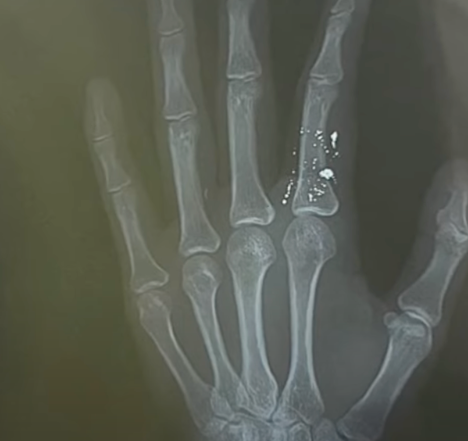

Ngón 2 bàn tay trái của người bệnh bị nhiễm độc thủy ngân

Kết quả quả chụp X-quang cho thấy hình ảnh ngón 2 bàn tay trái chứa nhiều hạt thủy ngân. Bệnh nhân được chuyển lên tuyến trên theo dõi, điều trị.

Bác sĩ Nguyễn Mạnh Chiến, Trung tâm chống độc, Bệnh viện Bạch Mai, cho biết tại đây bệnh nhân được chẩn đoán bị nhiễm độc thủy ngân với tình trạng ngón 2 bàn tay trái sưng nề, đồng thời trên phim chụp có rất nhiều hạt thủy ngân ở ngón tay chưa thoát được ra ngoài.